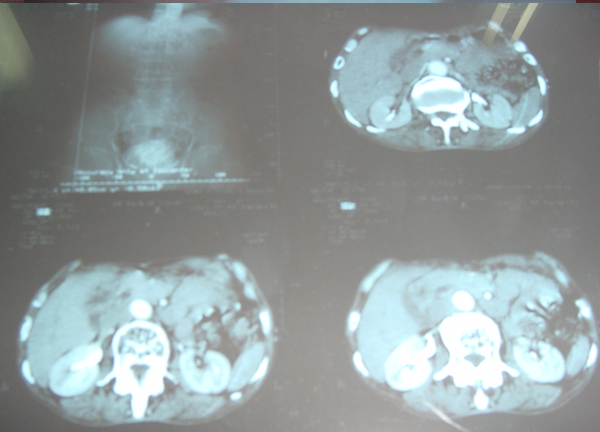

Case presentation

- Rajbir Singh, 60 yrs male.

- Abdominal pain for years now worsening.

- Severe COPD + PHT + CAD.

- USS abdomen for abdo pain – 7cm AAA.

- Pulsatile abdominal mass – non tender.

- All peripheral pulses palpable to ankles.

- No complications – blue toe syndrome.